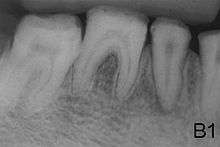

Amelogenesis imperfecta (AI) presents with a rare abnormal formation of the enamel[1] or external layer of the crown of teeth. Enamel is composed mostly of mineral, that is formed and regulated by the proteins in it. Amelogenesis imperfecta is due to the malfunction of the proteins in the enamel: ameloblastin, enamelin, tuftelin and amelogenin.

People afflicted with amelogenesis imperfecta have teeth with abnormal color: yellow, brown or grey; this disorder can afflict any number of teeth of both dentitions. The teeth have a higher risk for dental cavities and are hypersensitive to temperature changes as well as rapid attrition, excessive calculus deposition, and gingival hyperplasia.[2]